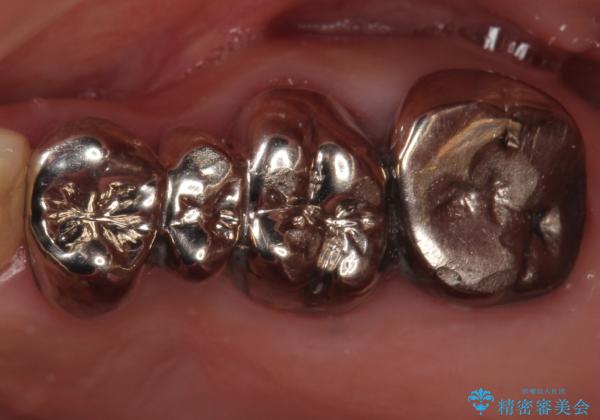

銀歯を白くしたい セラミックブリッジでの治療

- 銀歯を白くしたいとのことで来院。

左上が特に気になるそうであったためまず左上の奥歯から治療をしていここととなりました。

銀歯を除去し、土台の歯にに虫歯がないかを確認します。

今回は目立つ虫歯がなかったため、形を整えて白い被せものを装着しました。

他の銀歯も白くしていきたいとのことで、現在前向きに検討されています。